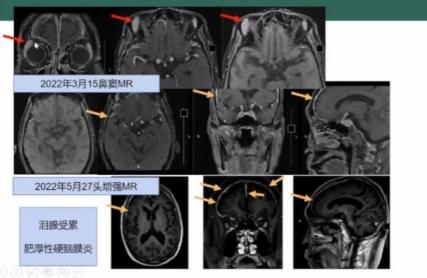

副鼻窦MRI平扫+增强(图1):双筛窦及上颌窦粘膜增厚:右泪腺增大,双腮腺、颌下腺饱满:右中耳乳突炎:颅内肥厚性硬脑膜炎。

图1 副鼻窦MRI平扫+增强PET-CT: